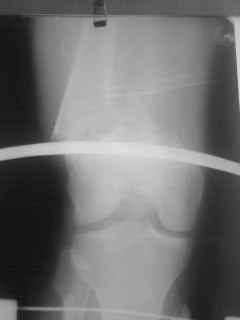

Уважаемый коллеги! Если внимательно проследить линию перелома проксимального отломка бедра и линию перелома дистального отломка по латеральной поверхности, то они конгруэнтны. В связи с этим возникает сомнение в наличие дефекта кости. Нужны более обширные рентгенограммы с захватом тазобедренного сустава и сравнение длины конечности. В любом случае, если предполагаете ретроградно БИОС,бедренный канал Вам нужно визуализировать, что бы на встретить "интересного клинического случая". А метод синтеза - тот которым располагаете и лучше владеете. Открытый перелом без явного инфицирования не противопоказание для погружного остеосинтеза. Можно вести и в АВФ.

о дальнейшей тактике лечения можно думать после четких проекций: на надколенник, профиль, осевой снимок нижней конечности. patella baja, УВО - может чисто проекционное? В плане пластики, по-моему, рекомендовано уже у МЕМ.